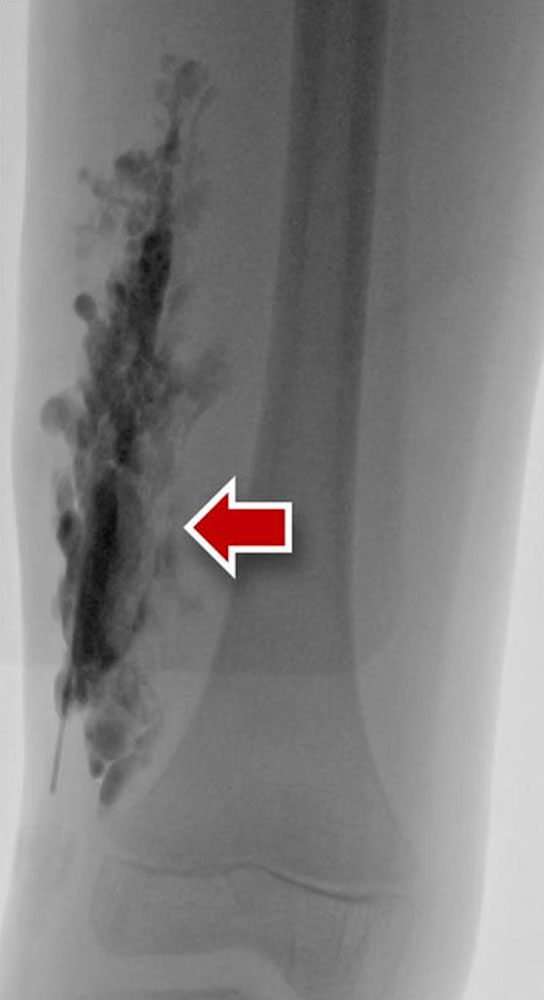

Phlebography/varicography is a radiological procedure for direct imaging of venous vessels. In this procedure, iodine-containing X-ray contrast medium is directly injected into the venous vascular system via a venous puncture. These procedures are used in most cases to assess the deep and superficial venous system of the upper and lower extremities. For imaging of the deep venous system of the leg a tourniquet is applied above the ankle to redirect the contrast after injection at the dorsum of the foot. Pathological venous vessels and venous malformations can also be punctured directly.

Venous malformations are typically tubular or lobulated, sponge-like dysplastic vascular spaces, which are almost always connected to very small or larger draining veins (communicating veins). Contrast filling defects within the venous malformation correspond to intraluminal thrombi or phleboliths. Direct puncture of the lesion with a needle and subsequent injection of contrast medium aims to identify larger veins of the malformation communicating with the deep venous system immediately prior to sclerotherapy. Any larger communicating veins should be closed. In addition, the contrast injection confirms the needle position and provides an estimate of the size and volume of the punctured part of the venous malformation.